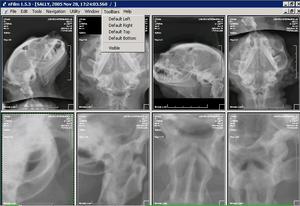

DICOM. La imagen DICOM se puede examinar de múltiples formas: ampliando, en copia negativa, realzando , etc.. Sólo se puede manejar con software DICOM. |

JPG: La imagen DICOM se puede exportar en formato convencional JPG para que se pueda leer con cualquier visor. |

NEURORADIOGRAFÍA: En neurología es de gran ayuda muchas veces el realizar copias en negativo para la observación de los contrastes mielográficos. |